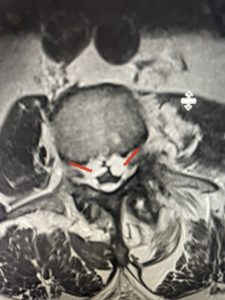

This 66 year-old male with Factor XI deficiency had originally had a decompressive laminectomy L2-S1 and in situ fusion about three years prior for severe thecal sac compression mainly due to severe epidural lipomatosis (Fig 4).

(Fig 4a) Sagittal (a) and Axial (b) T2-weighted lumbar MRI demonstrating severe spinal stenosis L2-5 (arrow)and extruded disc at L3-4 on axial image (arrow)

(Fig 4b)

Epidural lipomatosis is a relatively rare condition where normally present fat in the epidural space is hypertrophied and can cause severe thecal sac compression. It is generally deposited more in the lateral and dorsal epidural space. This can be caused by long term steroid use and obesity, but also can be idiopathic. He had done well until more recently had developed low back pain with bilateral thigh pain and numbness. He had difficulty walking because of the pain. A new MRI (Fig 5) revealed that he had developed severe degeneration of the L1-2 segment above his prior decompression and fusion with a large extruded disc/osteophyte, right greater than left with severe thecal sac compression. He also had some residual T12-L3 residual epidural lipomatosis.

He had failed conservative treatment consisting of neurontin, physical therapy and epidural injections. He underwent revision laminectomy T12-L3 to decompress and explore prior fusion. He did have significant epidural fat encountered particularly at L1-2. The fat in epidural lipomatosis has a much more firm, globular texture. It takes a while to search within the fat, gently dissecting with a Penfield 4, to finally find the thecal sac! We encountered a large subligamentous extruded fragment lateral to the thecal sac on the right above the take off of the L2 nerve root. We removed any more residual fat at the L2-3 level and T12-L1 and decompressed the sac well. On exploration of the prior fusion it was fairly solid, but had some gaps at L2-3 fusion mass. Therefore we added a T12-L3 in situ fusion to augment those gaps and because we were at the thoracolumbar junction we extended fusion to T12. Post operatively he had relief of his leg pain.

(Figs 5a): Sagittal (a) and axial (b) T2-weighted lumbar MRI demonstrating status post lumbar decompression and insitu fusion L2-5 now well decompressed (blue dash) with development of new (red arrow) severe stenosis and with superimposed right L1-2 disc herniation (blue arrow)

(Figs 5b)